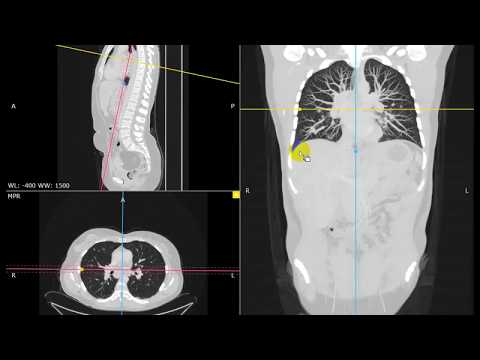

• استخدام برنامج RadiAnt DICOM Viewer لعرض الصور الطبية بدقة وفعالية

• تفسير الصور الطبية المختلفة مثل الأشعة السينية، الرنين، والتصوير المقطعي بشكل عملي

كورس اون لاين مجانا لتعلم RadiAnt Dicom Viewer عرض الأشعات RadiAnt DICOM Viewer ، برنامج عارض صور طبي يأتي بواجهة مستخدم رائعة وأداء رائع. يدعم البرنامج ملفات مختلفة معدة بأساليب وأجهزة مختلفة ، بما في ذلك التصوير الشعاعي الرقمي ، والتصوير الشعاعي للثدي ، والتصوير المقطعي المحوسب والرنين المغناطيسي ، والتصوير بالموجات فوق الصوتية ، وتصوير الأوعية الرقمية ، وكاميرات جاما ، والطب النووي ، والمزيد. بالإضافة إلى دعم التنسيقات المتعددة ، يتم توفير أدوات مفيدة لقياس ومعالجة الصور مثل السطوع والتباين والوضع السلبي ونافذة الإعداد المسبق لصور CT وتدوير الصورة وأداة القلم للرسم وأدوات أخرى.